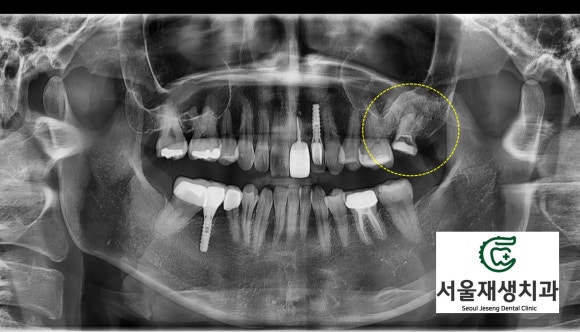

사진상 오른쪽 위에 보이는 치아입니다.

노란 점선 안에 있는 치아에 주목해주세요.

먼저 정밀 검사를 통해 치아 상태를 꼼꼼히 살펴보았습니다.

일반 평면 엑스레이에서 보기에도 뿌리 끝 염증 사이즈가 상당합니다.

신경치료용 CT를 촬영하니 상악동으로 염증이 파급되려는 상태였고, 기존 신경치료의 흔적도 확인할 수 있었습니다.